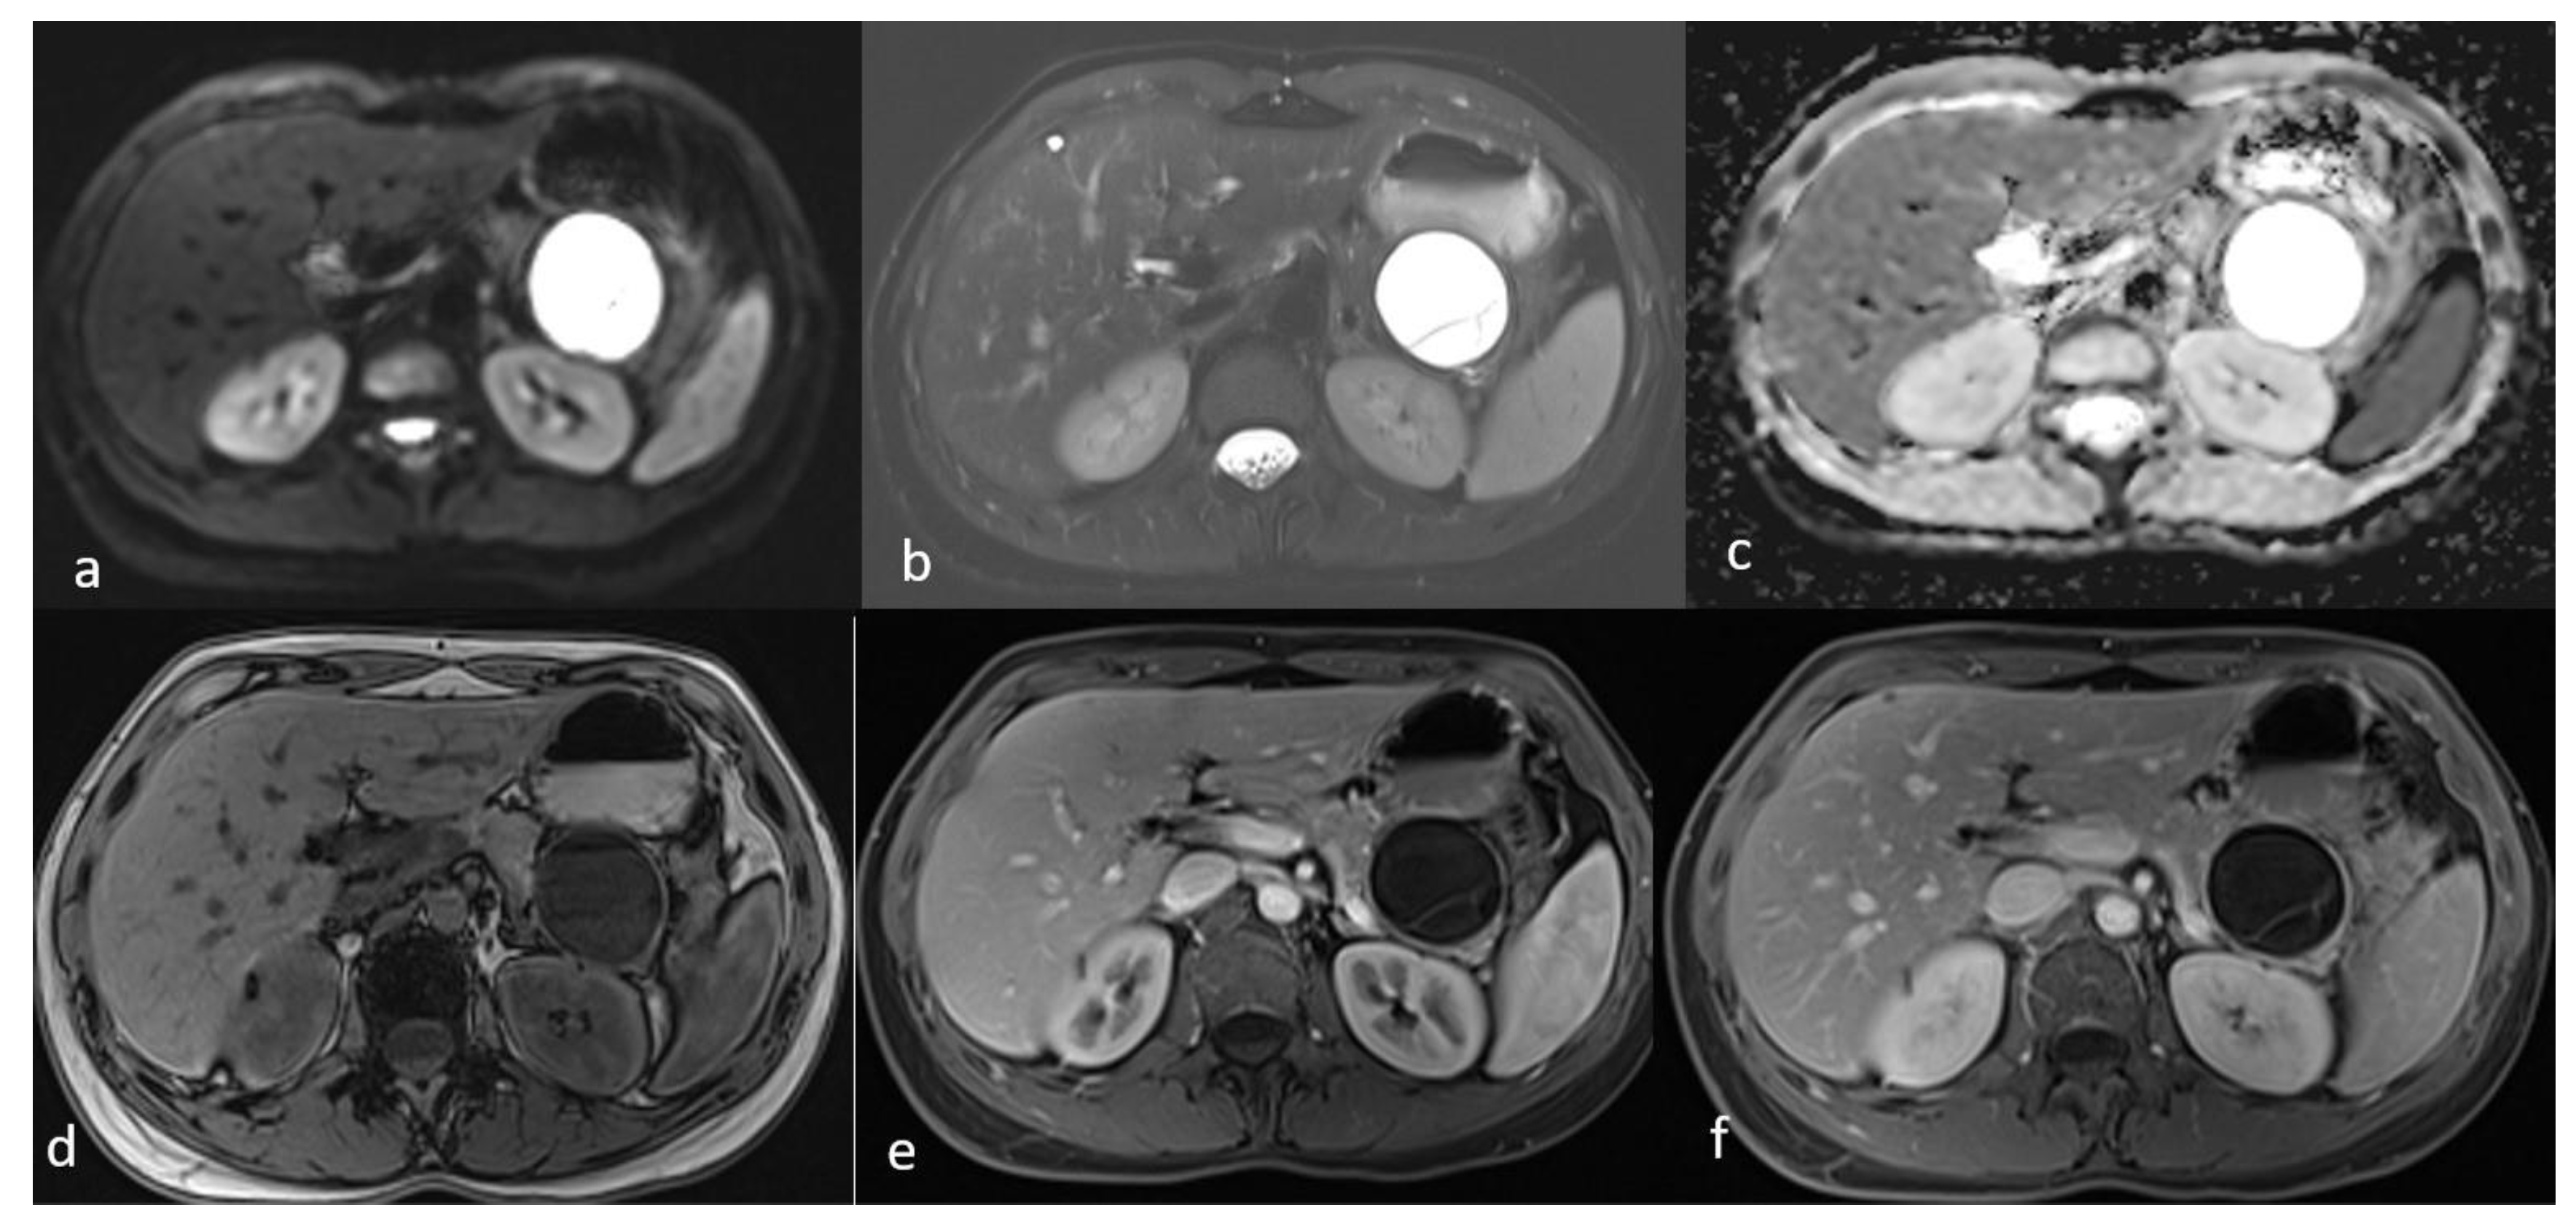

An MRI of the abdomen, performed approximately one year prior to admission, revealed a cystic thin-walled formation with internal septa, located in the dorsal part of the tail of the pancreas. The lesion measured approximately 3.9 cm in diameter and exerted pressure between the pancreas and the greater curvature of the stomach. The walls and internal diaphragms of the cyst showed enhancement post-contrast injection. There was no evidence of pancreatic duct dilation. Differential diagnoses at this stage included pancreatic cystic lesions such as cystadenoma, though the patient’s age was considered atypical, as well as other lesions like cystic lymphangioma or replication cysts. Additionally, incidental findings of mild hepatomegaly and a 9.5 mm hemangioma in the eighth hepatic segment were noted, along with small lymph nodes (Figure 2). In the absence of high-risk features or significant symptoms, a watch-and-wait approach with periodic monitoring was deemed appropriate.

Figure 2.

First MRI axial sequences of the upper abdomen. (a) T2 Blade axial sequence showing hyperintensity of the cyst (white arrows). (b,c) DWI and ADC showing no internal restriction of the cystic lesion. (d) T1 Vibe showing a hypointense cystic lesion at the tail of the pancreas. (e,f) T1 Vibe post-contrast at arterial and venous phases showing only minimal enhancement of the cyst wall and the septations with no internal solid component.